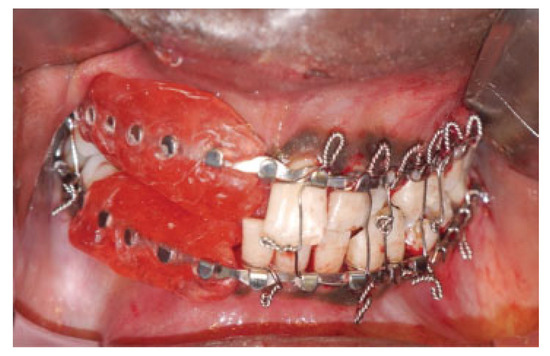

Orbitozygomatic fractures are one of the most common maxillofacial injuries encountered. This study aims to investigate and review the management and complications of orbitozygomatic fractures at the Royal Brisbane and Women’s Hospital (RBWH). Specif...